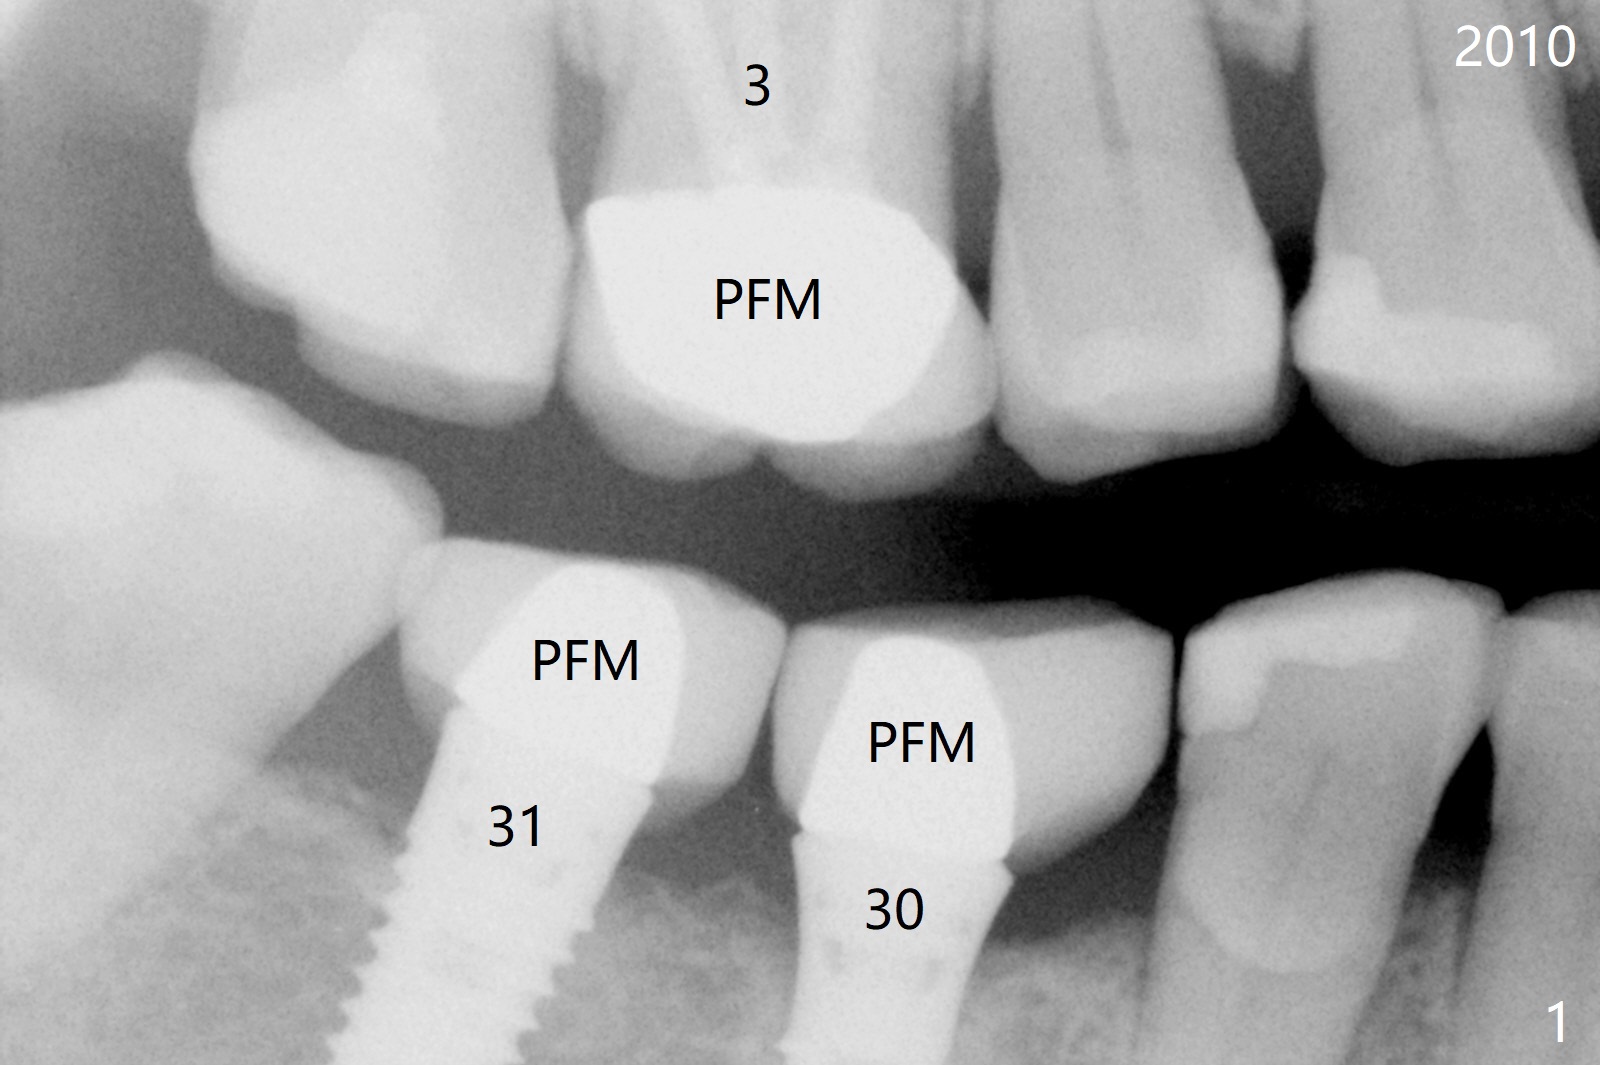

A 50-year-old woman is a bruxer. There are 3 PFM crowns at #3, 30 and 31 (Fig.1). A full metal crown is changed at #31 because of porcelain chip 3 years later (Fig.2). A Zirconium crown is fabricated at #2 after tooth fracture; porcelain chips at #30 and the PFM crown is removed (Fig.3) for Zirconium one (Fig.4). It appears that the weakest link lies between two materials (porcelain and metal of PFM crown) under heavy occlusion and when the implant has no flexible mechanism (periodontal ligament). Either full metal crown or Zirconium one is a suitable crown material for bruxer. Note the dense bone around the implant at #30 (Fig.4 (bruxism)).